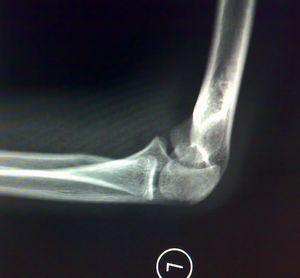

标题: X7845:M 16岁 外伤就诊。

影像所见:左肱骨远端隐约可见自外上髁向髁间走行不规则骨质透亮线,侧位显示肱骨前线欠光整。未见脱位征象。骨骺发育未见异常。

印象:左肱骨远端骨折不除外。

建议:斜位投照或ct。

我怎么感觉肱骨外上髁上方皮质有裂隙啊,建议一周后复查。

髁上骨折?

加照对侧,感觉肱骨外上髁上方内侧骨骺旁显示低密度负影。

外上髁骨折?